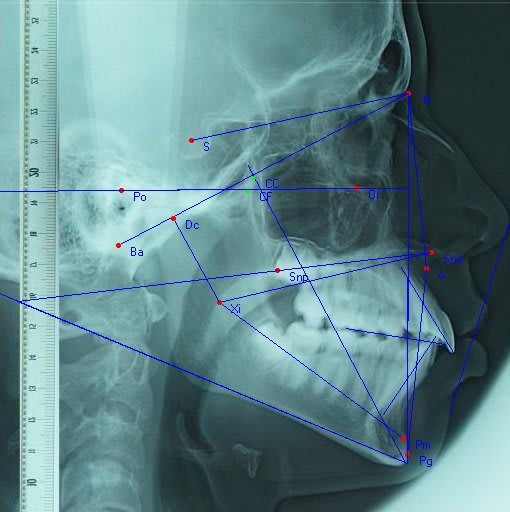

Bon, on passe a ricketts

Angle facial : 90 89 position norm mdbule

Axe facial : 90 87 direction norm

Divergence md : 29 24 legere hypodivergence

Haut faciale inf: 47 48 mesofacial

convexité :-1 7 profile tres convexe

axe inc inf : 22 27 protrusive

levre inf :-11 6 profile tres convexe

Florent ricketts m5hxw8 - Eugenol